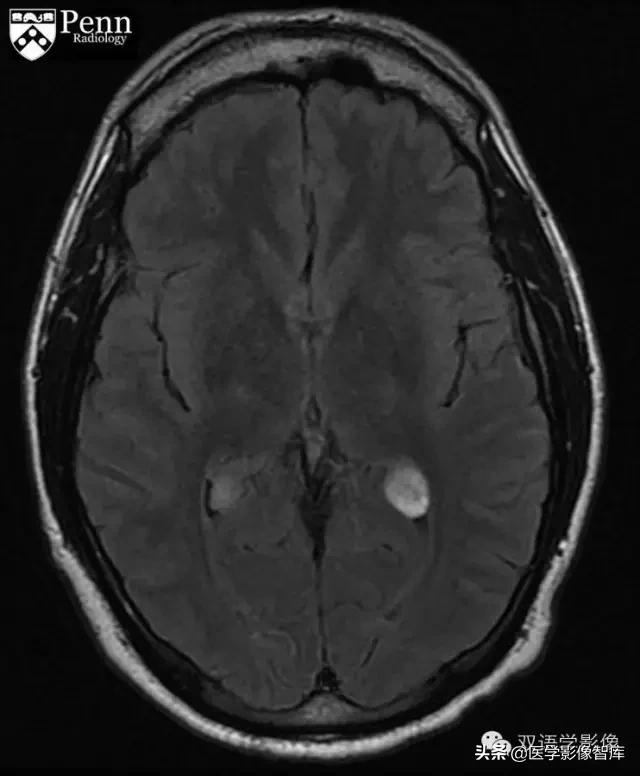

Brain fluid-attenuated inversion-recovery (FLAIR) MR images are shown below.

Brain MRI shows cysts in the choroid plexi in the bilateral atria of the lateral ventricles.脑部MRI示双侧侧脑室腔内脉络丛内囊性病变。The cysts demonstrate mild high signal on FLAIR, restricted diffusion, and mild peripheral and central enhancement.FLAIR序列呈略高信号,DWI示弥散受限、呈高信号。增强扫描病灶周边和内部轻度强化。 There is no hydrocephalus.患者无脑积水表现。

Choroid plexus xanthogranulomas are cysts that usually range in size from 2 mm to 8 mm and rarely are larger than 2 cm. 脉络丛黄色肉芽肿是大小约2-8mm的囊性病变,很少超过2cm。They are usually bilateral and multiple.通常为多发、双侧对称性发病。On CT, the cysts are isodense or slightly hyperdense to cerebral spinal fluid. Irregular and peripheral calcium in these cysts is common in adults.CT上,囊肿与脑脊液相比呈等或略高密度,成年患者的病灶周边可见钙化。 On MRI, 60% to 80% show restricted diffusion; usually iso- or hypointense but can be hyperintense on FLAIR; and enhancement (ring, nodular, solid) varies from none to strong.MRI上,约60%-80%的病灶弥散受限、DWI呈高信号。通常病灶呈等或稍低信号,但FLAIR可呈高信号。增强扫描病灶可无强化,也可以呈环形强化、结节状强化、实性部分强化等多种强化方式。